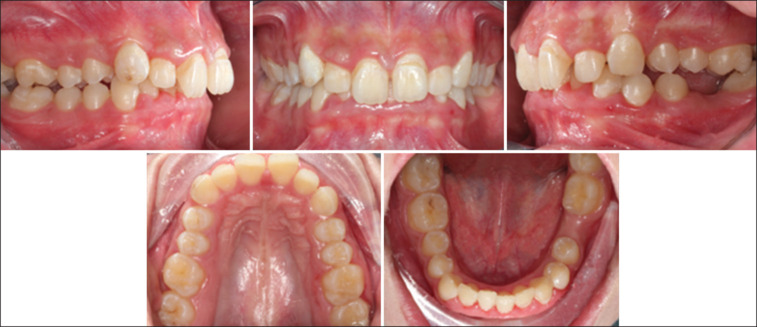

This case report details the treatment of a 23-year-old female patient with Class II division 2 malocclusion with a Class II skeletal base due to a retrognathic mandible. The condition was further complicated by a complete overbite, absence of tooth #36, and a gummy smile. The Forsus appliance has shown to be effective in correcting Class II malocclusion in adult patients, with significant improvements in bite and facial esthetics. The use of temporary anchorage devices for intrusion resulted in lower overbite and increased actual intrusion compared with alternative methods for intruding upper incisors.